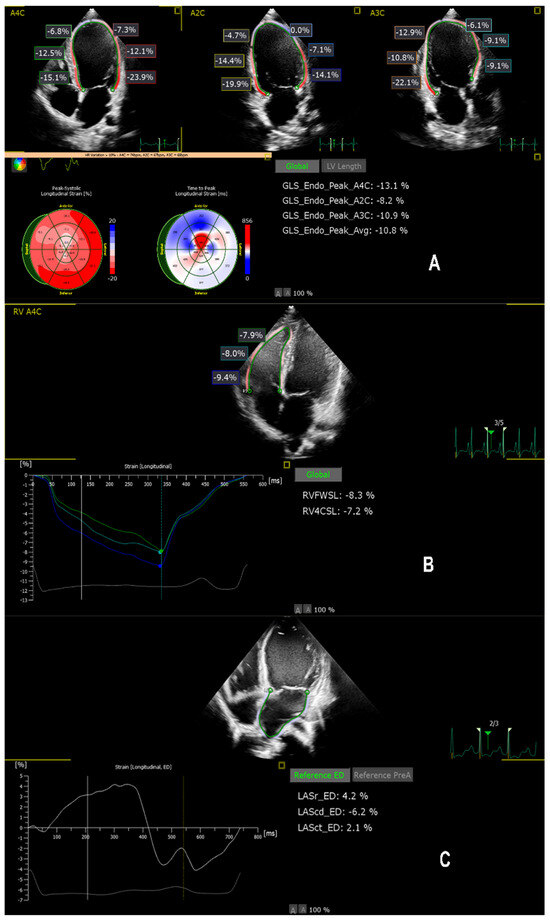

Dilated cardiomyopathy (DCM) in children is rare, but carries a high risk of progression to advanced heart failure (HF) and heart transplant (HTx). Improved short-term risk stratification is essential; however, robust pediatric prognostic tools remain limited. We aimed to evaluate the 1-year prognostic value of multichamber speckle-tracking echocardiography (STE) and biomarkers, including age-adjusted N-terminal pro-B-type natriuretic peptide (NT-proBNP) and vitamin D, in children with DCM. In this single-centre prospective cohort study, 29 children with idiopathic DCM and 27 age- and sex-matched healthy controls underwent standardised clinical, laboratory, and echocardiographic assessment. The primary endpoint was a 12-month composite of implantation of an implantable cardioverter-defibrillator (ICD), left-ventricular assist device (LVAD), HTx, or all-cause mortality. During a 1-year follow-up, 9/29 (31%) DCM patients experienced major events. Compared with event-free patients and controls, children with events had more impaired LVGLS (−5.99 ± 2.45% vs. −13.44 ± 6.88% and −19.98 ± 3.25%), lower LASr (10.97 ± 7.67% vs. 25.36 ± 10.28% and 44.0 ± 11.43%), and reduced RVFWSL (−15.32 ± 5.24% vs. −23.13 ± 8.55% and −24.78 ± 4.45%; all p < 0.01). Zlog NT-proBNP was markedly higher in the event group (5.37 [5.00–6.08] vs. 2.28 [0.71–3.68] and 0.14 [−0.02–0.88]). LVGLS, Zlog NT-proBNP, and LASr showed excellent discrimination for 1-year events (AUC 0.91, 0.91, and 0.87, respectively), with clinically applicable cut-offs (LVGLS ≥ −8%, Zlog NT-proBNP ≥ 4.6, LASr ≤ 21%). In conclusion, multichamber strain imaging combined with age-adjusted NT-proBNP provides clinically relevant, exploratory markers for short-term risk stratification in pediatric DCM, supporting earlier intensification of follow-up and timely referral for advanced heart failure therapies. These findings warrant validation in larger multicenter cohorts. Full article

Background: Right-ventricular (RV) involvement is starting to gain recognition in pediatric dilated cardiomyopathy (DCM), but its deformation characteristics and its relationship to functional status remain insufficiently defined. Methods: Twenty-nine children with primary DCM were compared with age- and sex-matched healthy controls. Conventional echocardiography [...] Read more.

Background: Right-ventricular (RV) involvement is starting to gain recognition in pediatric dilated cardiomyopathy (DCM), but its deformation characteristics and its relationship to functional status remain insufficiently defined. Methods: Twenty-nine children with primary DCM were compared with age- and sex-matched healthy controls. Conventional echocardiography and two-dimensional speckle-tracking echocardiography (2D-STE) were performed. Segmental deformation (basal, mid-ventricular and apical levels) was analyzed using a linear mixed-effects model. Associations between strain indices and advanced functional limitation (NYHA/Ross Class III-IV) were evaluated using exploratory logistic regression and ROC analysis. Results: Children with DCM showed significant impairment in both ventricles. Conventional parameters (TAPSE, tricuspid E/A ratio, RV E′ velocity, and LV ejection fraction) were reduced. Right ventricular strain was significantly lower in DCM compared with controls (p < 0.05). Segmental analysis demonstrated a basal-predominant reduction in RV strain. Right-ventricular free-wall longitudinal strain correlated with RV S′ (r = −0.49), RV E′ (r = −0.46), LVGLS (r = 0.79) and LV ejection fraction (r = −0.63, all p < 0.05). In univariable analysis, RVFWSL predicted advanced functional class (OR 1.13 per 1% decrease, p = 0.026), while LVGLS remained the independent predictor in the multivariable model. A combined model incorporating RVFWSL and LVGLS demonstrated excellent discriminative accuracy (AUC 0.95). Conclusions: Pediatric DCM is characterized by RV involvement with a distinct basal-dominant deformation pattern. Biventricular strain assessment improves the identification of children with advanced functional class and may enhance functional stratification beyond conventional indices. Full article